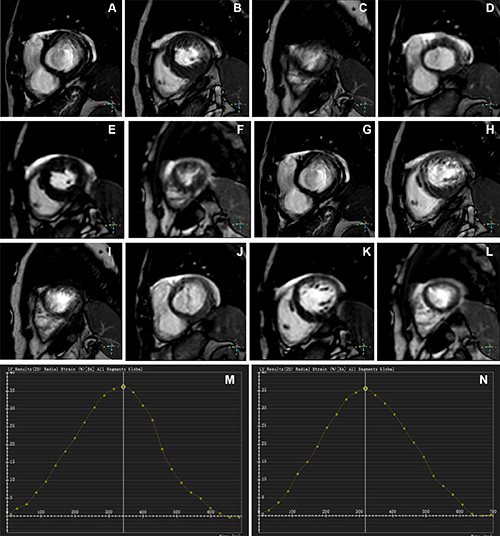

Figure 2. Representative images of participants with difficulty with breath holding and arrhythmia. In the lower right corner of A–L, the position coordinates of the images are marked. Short-axis (SA) view images in the end-systole (A–F) and end-diastole (G–L) phases in participants with atrial fibrillation. (A–C, G–I) Balanced steady-state free precession (bSSFP) cardiac cine. (D–F, J–L) Deep learning–enhanced compressed sensing (AI-CS) single-shot cardiac cine. In contrast to AI-CS single-shot cardiac cine, endocardial contours were challenging to identify on conventional segmented cine in midventricular and apical sections. (M) Line graph of time curve during the whole cardiac cycle obtained from bSSFP cardiac cine. (N) Line graph of time curve during the whole cardiac cycle obtained from AI-CS single-shot cardiac cine. LV = left ventricle., 2D = two-dimensional.